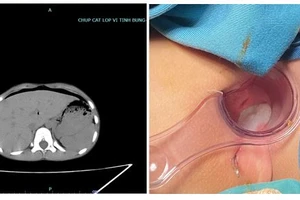

Trẻ nhập viện trong tình trạng mi sưng nề, chảy nước mắt, khó mở mắt, kết mạc cương tụ mạnh, giác mạc có vết thương xuyên thủng, có dị vật cứng ghim vào vết thương, giác mạc phần quanh vết rách mờ đục, phần giác mạc còn lại phù nhẹ.

Bệnh nhân được chỉ định phẫu thuật cấp cứu loại bỏ dị vật và khâu phục hồi vết rách giác mạc.

Dị vật được lấy ra là ruột bút chì dài gần 1cm. Sau phẫu thuật, sức khỏe bệnh nhi ổn định.

Bệnh nhi 9 tháng tuổi bị ruột bút chì đâm xuyên thủng nhãn cầu mắt phải. Ảnh: BVCC